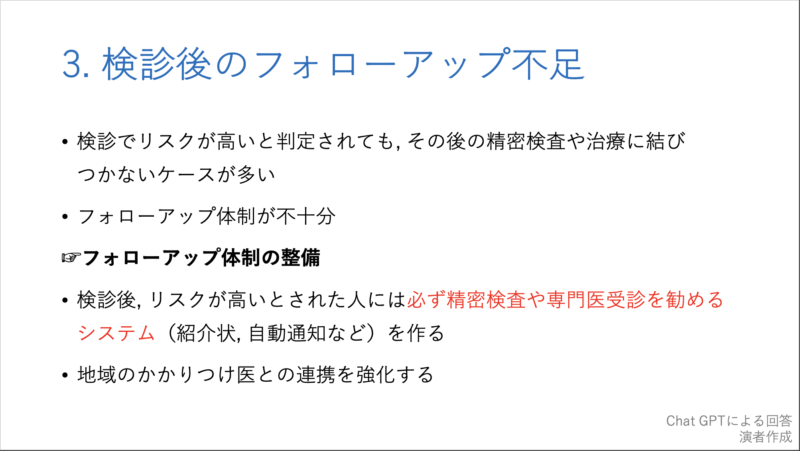

20時過ぎから, 私がclosing remarksとして, 10分で骨粗鬆症検診の問題点とその対策, および各県庁所在地での現状について, チャットGPTからの回答をからめてお話ししました. 途中で, 自分の大腿骨頚部骨折のことも取り上げました.